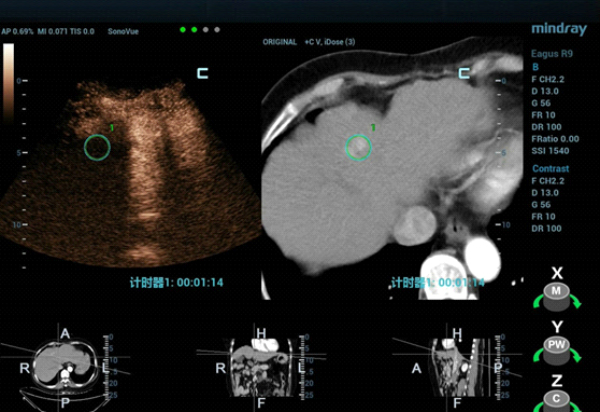

The patient was scheduled for ultrasound-guided microwave ablation (MWA), however, as the lesion could not be seen on conventional ultrasound, fusion imaging combining ultrasound imaging and contrast-enhanced CT (Clip 1, Figs. 4-7) was used to ensure accurate positioning of the microwave antenna.

The tumor was isoechoic and could not be clearly displayed using 2D grayscale ultrasound, therefore using conventional ultrasound guidance alone could result in inaccurate positioning and incomplete ablation. However, Fusion Imaging combining real-time ultrasound with the contrast-enhanced CT dataset allowed for accurate antenna positioning and successful treatment of the lesion by percutaneous MWA. CEUS was used pre-procedure to confirm tumor location and post-procedure to evaluate the ablation zone and ensure the efficacy of the treatment.